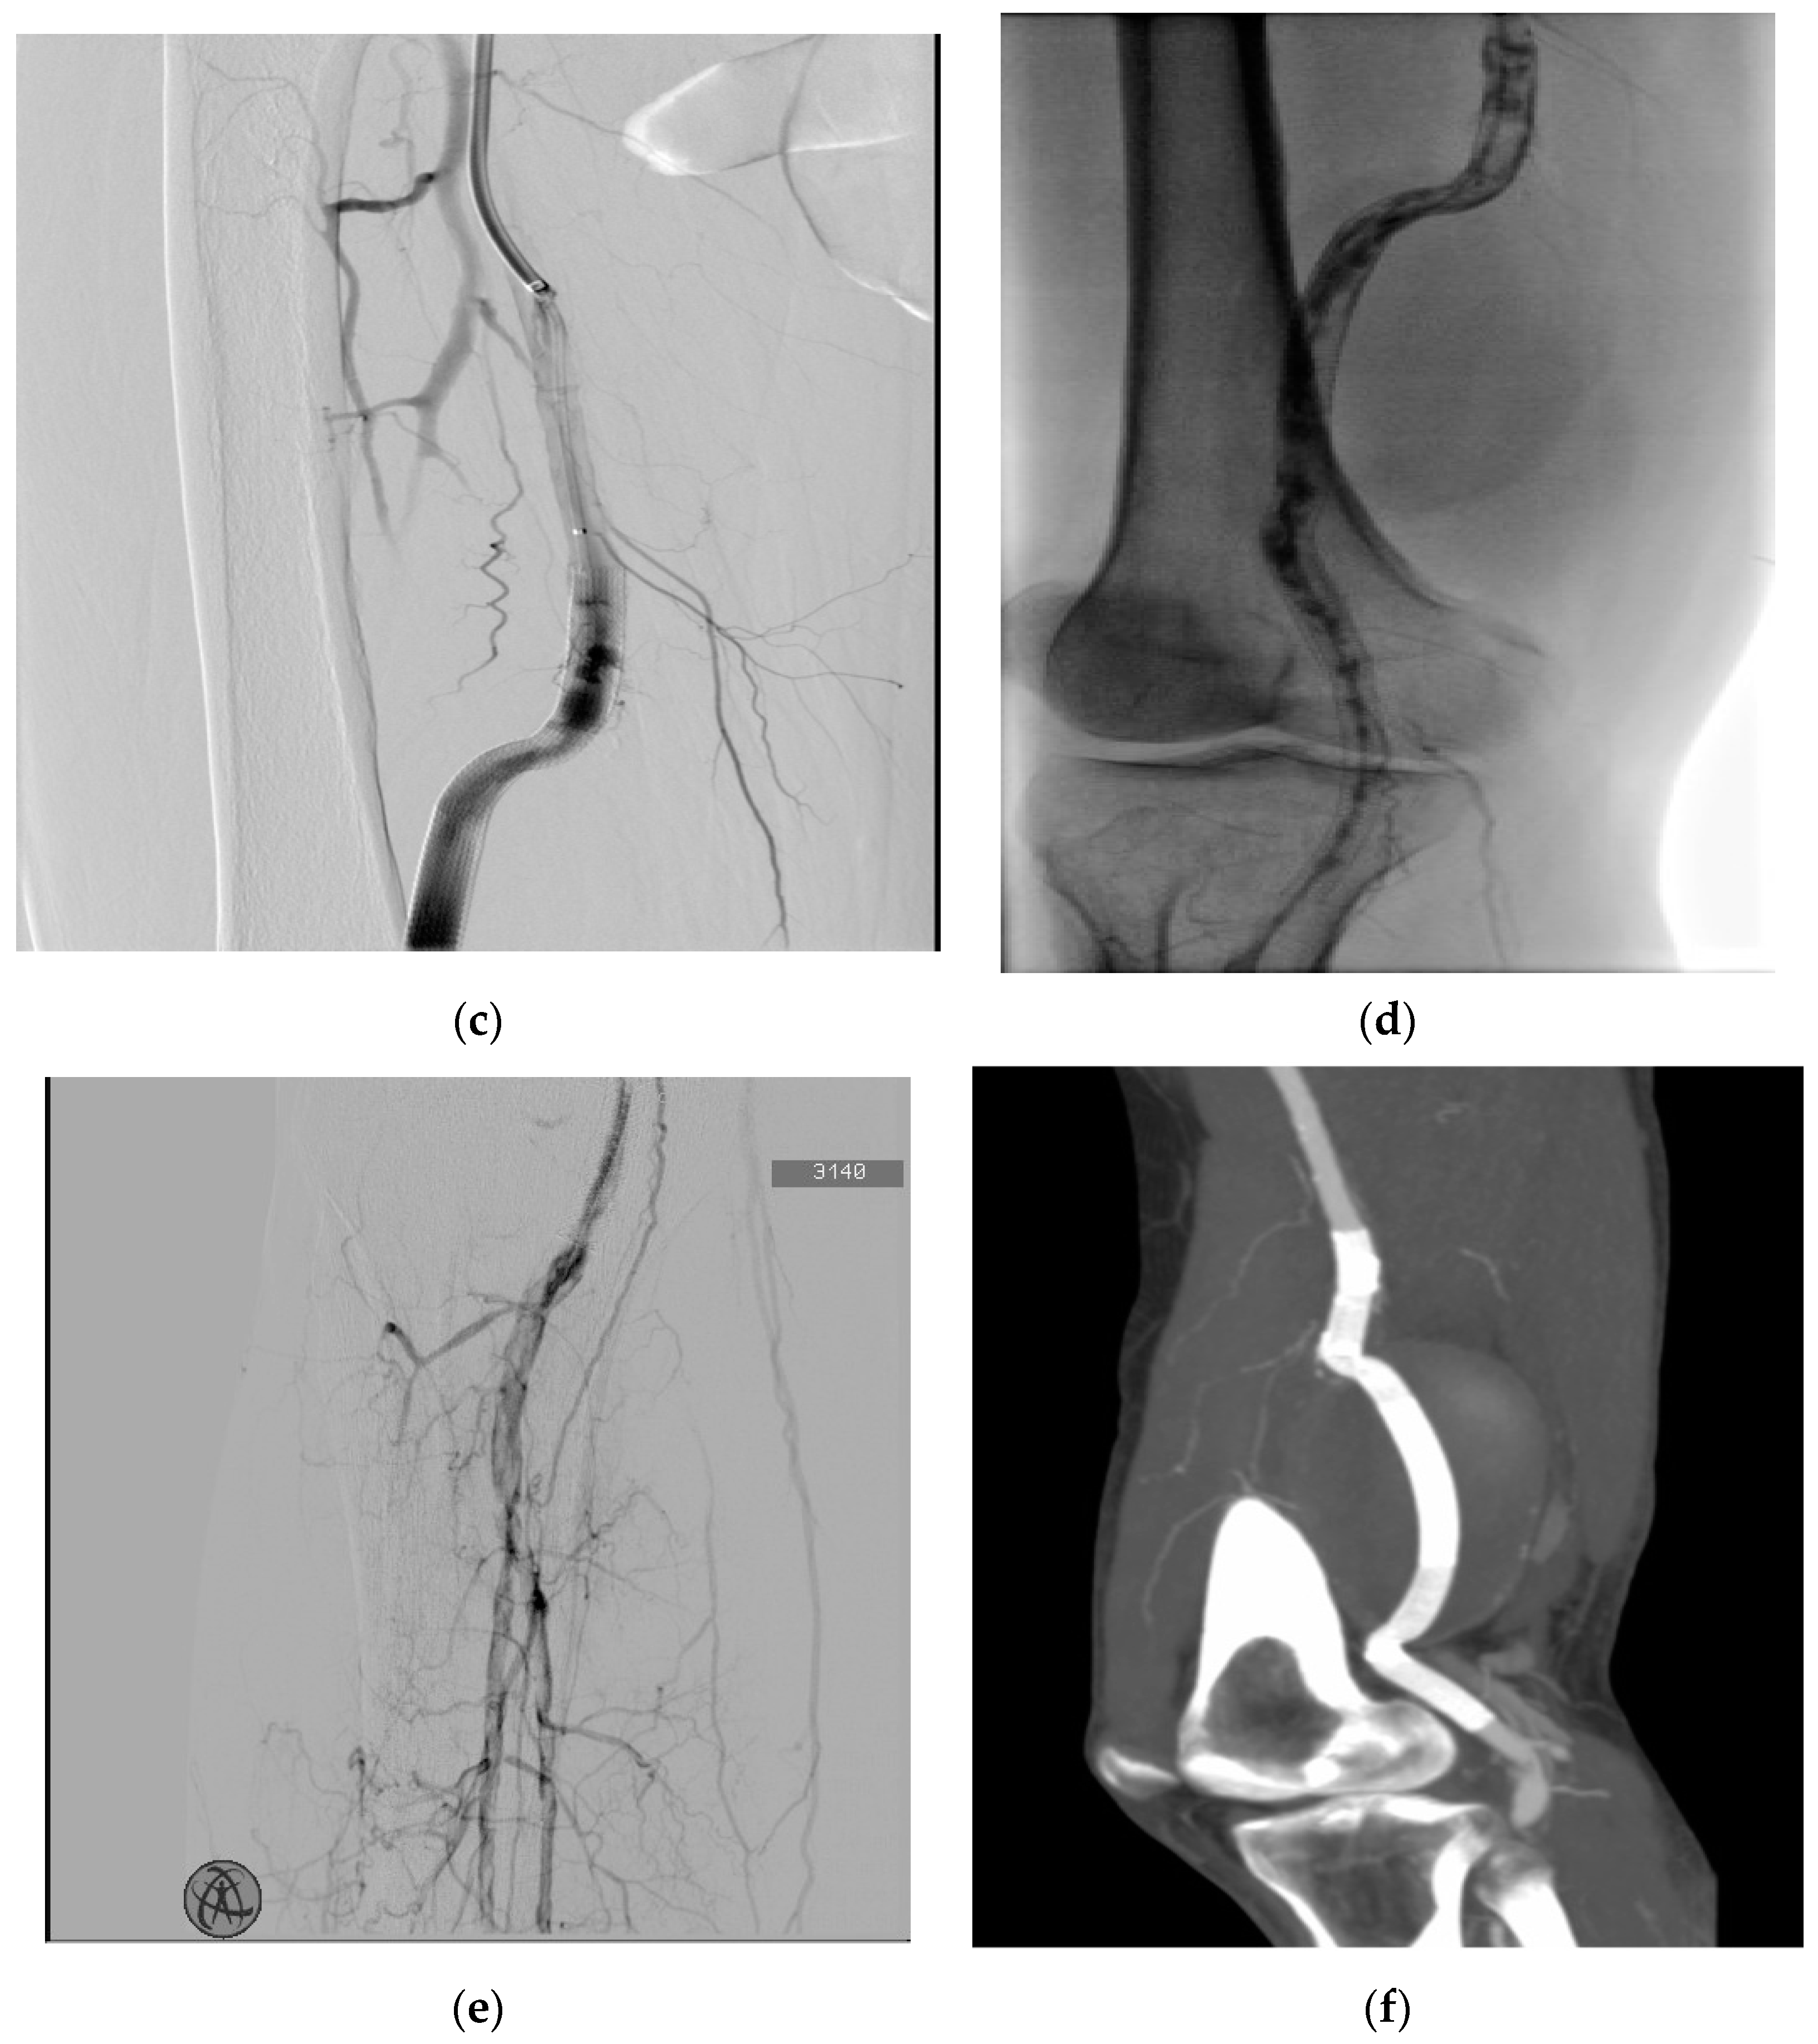

A 58-year-old man was admitted to the emergency room (ER) due to right lower extremity pain and pallor, involving the right leg, with motility and sensitivity reduced. An urgent CTA scan revealed a ruptured right PAA with poor below-the-knee (BTK) run-off vessels (Figure 1a). The patient underwent emergent hybrid treatment with a popliteal artery and distal vessel surgical embolectomy/thrombectomy using a Fogarty© catheter, followed by an endovascular procedure with PAA exclusion using a VIABAHN™ endoprosthesis and Supera stent for the distal landing zone (Figure 1b). After two years, the patient complained of severe claudication; an ultrasound exam revealed severe intrastent restenosis (Figure 1c). The patient underwent an endovascular procedure with percutaneous transluminal angioplasty (PTA), using a drug-eluting balloon in an intraoperative complication with distal vessel thrombosis (Figure 1d), which was solved by thromboaspiration and intra-arterial thrombolysis treatment with urokinase for 48 h. The postoperative image examinations recorded a good recovery of artery patency, and the patient was discharged on the fourth postoperative day. Five days later, the patient was re-admitted to the hospital for acute right inferior limb ischemia. Again, a conservative approach was done using 24 h intra-arterial thrombolysis and two adjunctive VIABAHN™ endoprosthesis was implanted because of disconnection between the VIABAHN™ that had previously been implanted. After two months, the patient returned to the hospital for the third time, presenting pain, hyperemia, and swelling of the right leg. A CT scan showed a fluid-corpuscular collection surrounding the endoprosthesis, which was related to the aneurysmal abscess collection of the right superficial femoral (SFA) and popliteal arteries (Figure 1e). The patient was admitted to our department to investigate the local popliteal abscess. Working with the infectious disease department, we took three sets of haemocultures, which tested positive for Staphylococcus capitis. We then performed local drainage with a puncture in the proximal area of the abscess and it revealed Staphylococcus capitis infection. We discussed our case with a multidisciplinary team, and we felt it was appropriate to start antibiotic therapy with daptomycin and then proceed to open surgery. After two weeks of prophylactic antibiotic therapy, the patient underwent a surgical conversion with the complete explantation of endovascular material (Figure 2b,c), and we performed a femoropopliteal bypass using an autologous vein (Figure 2d), with good patency of the downstream vessels after surgery.

Figure 1. (a) Preoperative CTA, showing the ruptured PAA in the lateral projection and a focal rupture in the rectus femoris muscle in the axial projection in the yellow box marked by narrowing. (b) Final intraoperative radiographic control showing the VIABAHN™ endoprosthesis and Supera stent in the popliteal artery after the first endovascular emergency procedure. (c) An intraoperative angiography through the catheter shows proximal and (d) distal intrastent thrombosis. (e) Intraoperative complication with thrombosis of the anterior tibial artery and peroneal trunk. (f) Computer tomography angiography shows a perianeurysmal collection of approximately 9 cm and endovascular bypass patency.